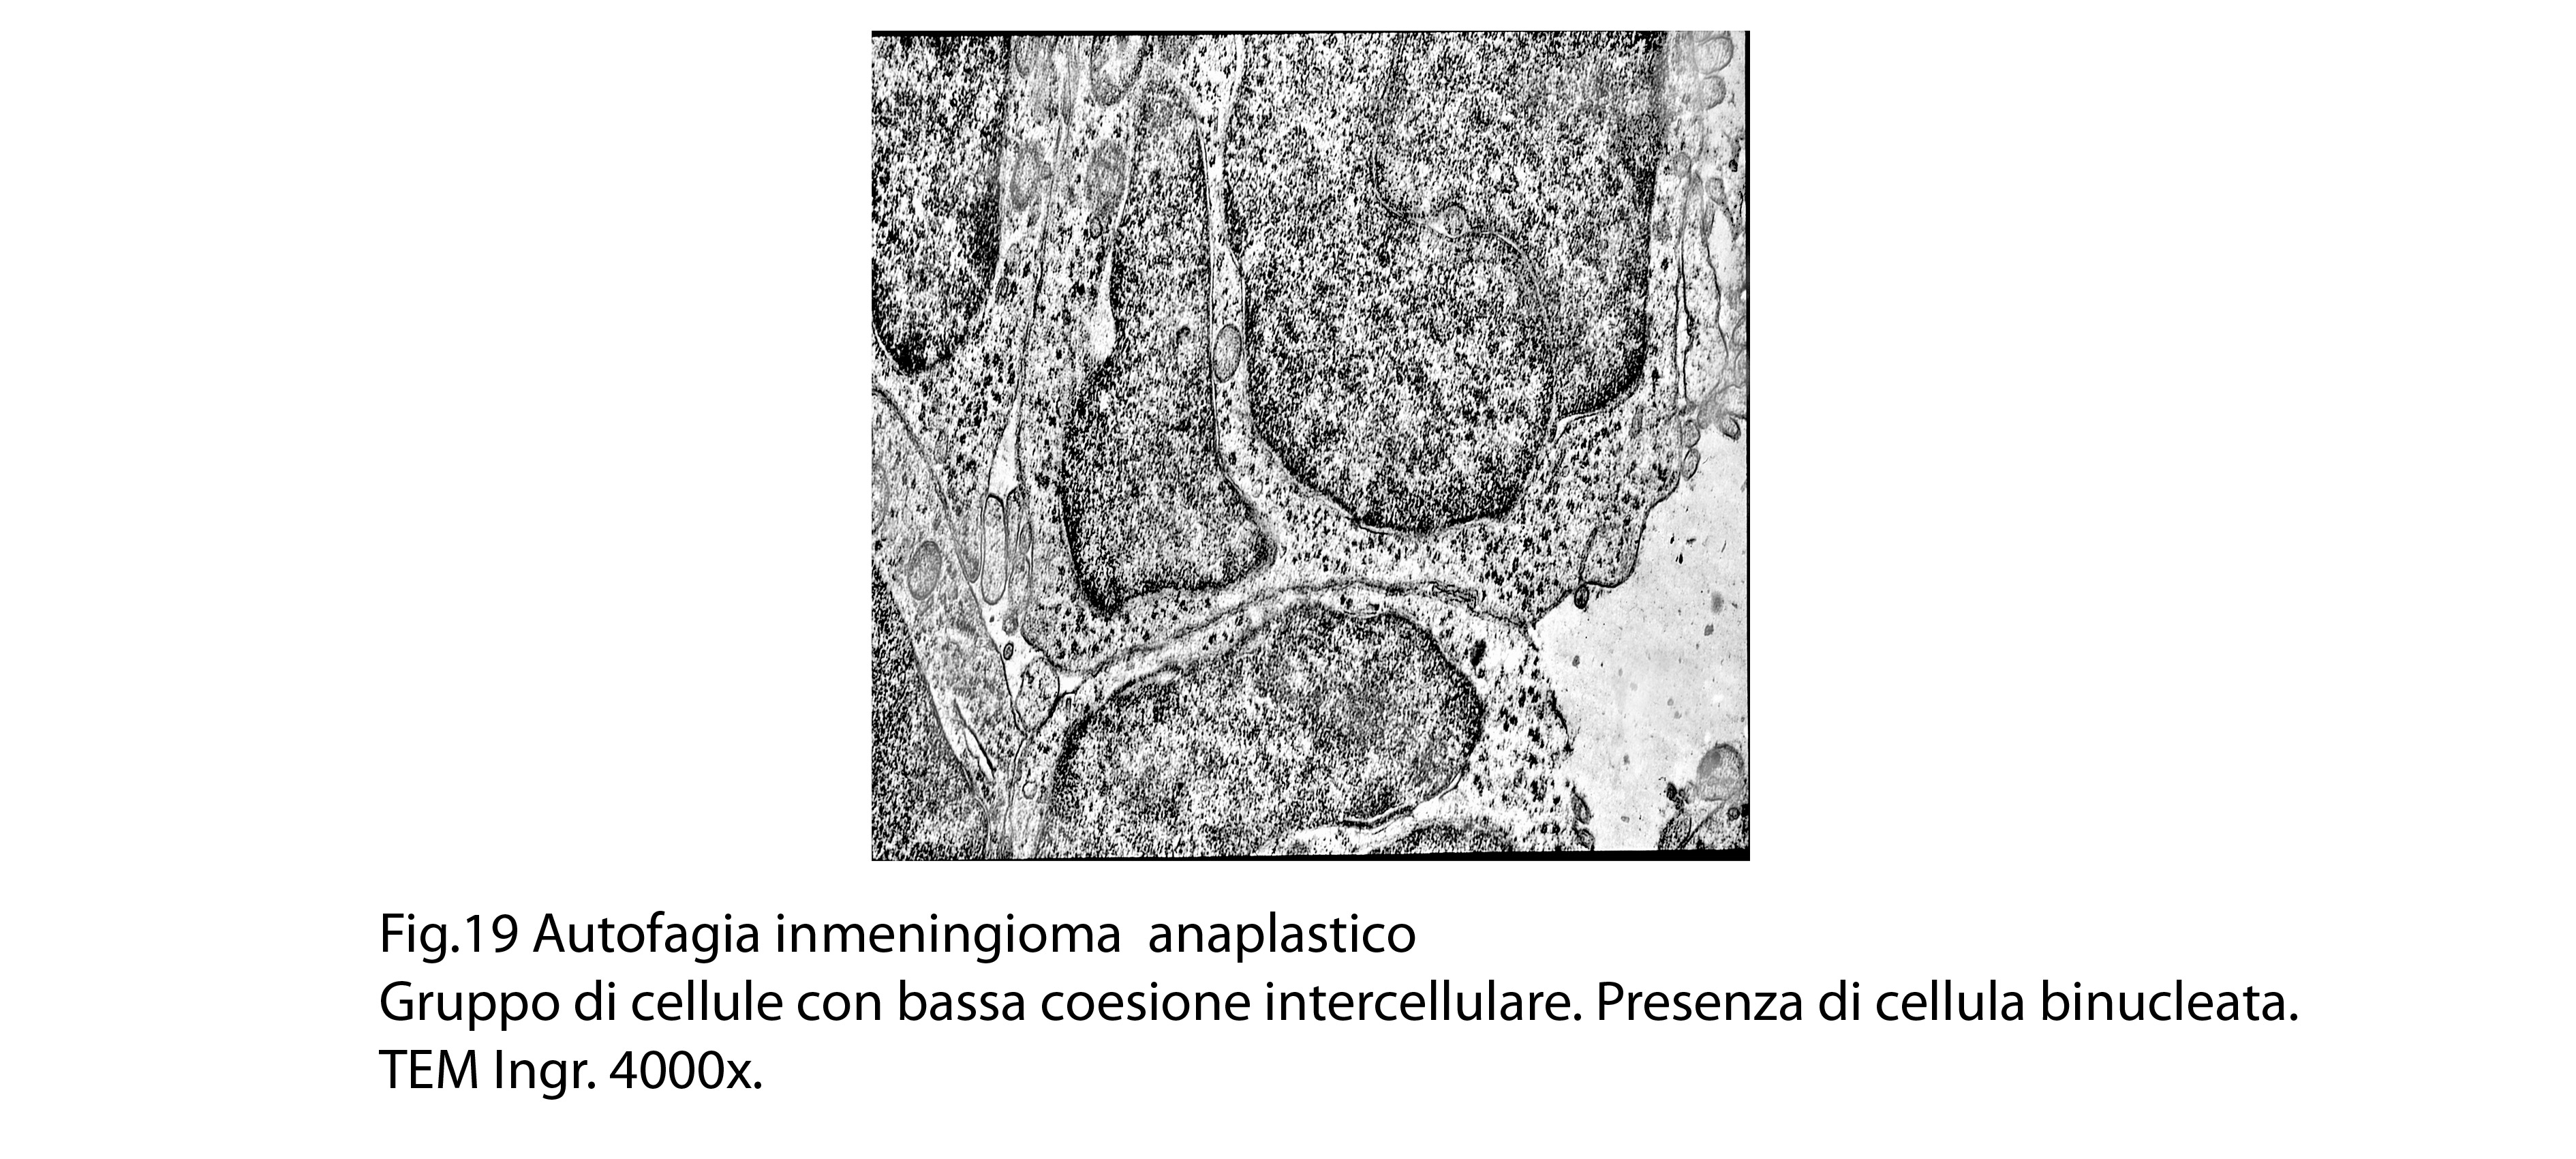

B) FOCOLAI DI AUTOFAGIA IN MENINGIOMI ANAPLASTICI

La popolazione cellulare dei meningiomi anaplastici è data da elementi di piccole e medie dimensioni che si dispongono spazialmente in aggregati informi. Ciascuno di essi ha una forma irregolarmente cuboide o poligonale e soprattutto è caratterizzato da una esigua quota citoplasmatica esigua e da una voluminosa massa nucleare.

Al microscopio elettronico,il citoplasma appare compatto ed il citosol contiene pochi mitocondri, scarso reticolo endoplasmatico ed ergastoplasma, discrete quote di ribosomi liberi e di microtubuli.

Molto frequentemente si riscontrano elementi i quali evidenziano una condizione di cellula binucleata.

Non mancano elementi caratterizzati da un citoplasma trasformato in piccoli ammassi informi per processi di necrobiosi.

Le numerose osservazioni ultrastrutturali condotte su casi di meningiomi anaplastici hanno evidenziato in modo ripetitivo gli abituali caratteri di cellule con tale morfologia e in nessun campo hanno evidenziato focolai riferibili a processi di autofagia.